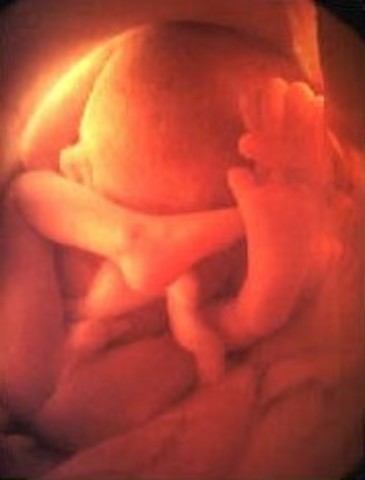

• Week Thirteen: Baby Flexes and Kicks

Week Thirteen: Baby Flexes and Kicks

Ribs are starting to appear and bones are replacing cartilage. The baby is able to open and close their mouth.

• Week Fourteen: Hormones Start Up

Week Fourteen: Hormones Start Up

The baby's facial features start to become more developed. The kidneys start to produce urine.

• Week Fifteen: Bones and Muscles Grow

Week Fifteen: Bones and Muscles Grow

The baby is able to move and make their hand into a fist. Their skin is still pretty thin.